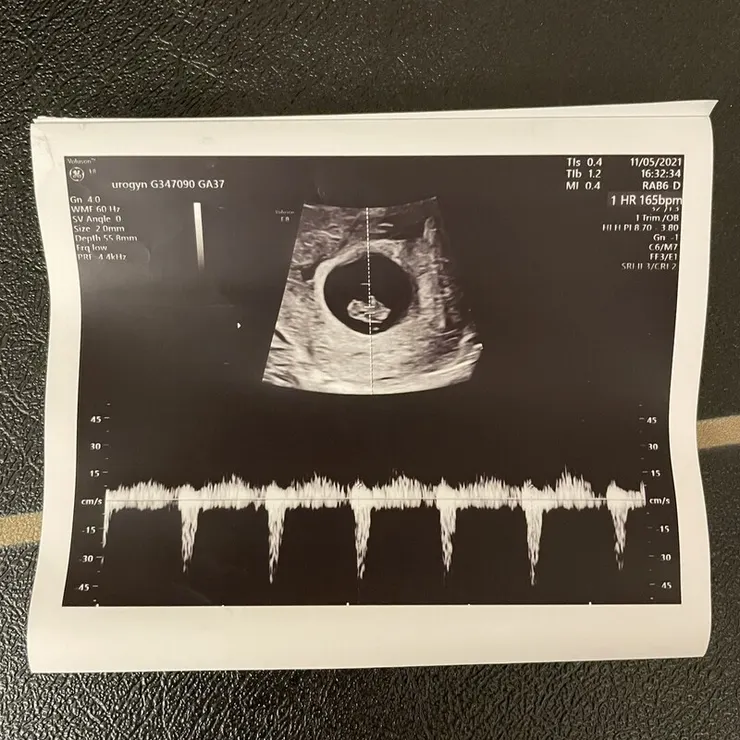

【第8周~心跳砰砰砰&媽媽手冊】

這周開始我換去台大生醫園區給林明緯醫師檢查

順利聽到心跳了(感動QQ) 林醫師也檢查確認著床位置正常! (呼~

拿到媽媽手冊的感受也好奇妙~~~ 這時候寶寶已經可以說是胎兒囉!

同時醫生也確定了預產期,接下來每周的檢查都會看寶寶成長有沒有符合週數